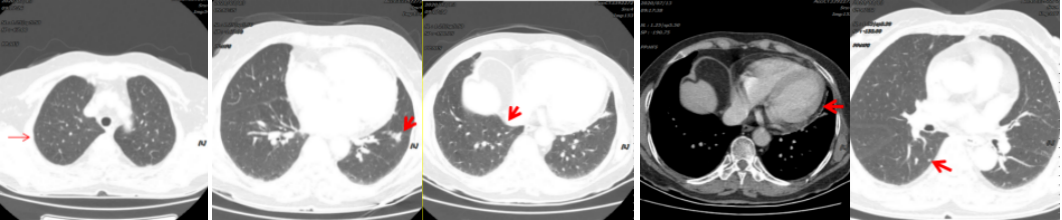

病例简介 该病例是一个肺腺癌(cT4N0M1a)IVa期患者,合并有高血压、冠心病、糖尿病。一线治疗前基因检测结果提示EGFR 19del(+)。一线治疗(埃克替尼片125mg tid)疗效评估为PR、PFS 22个月。一线治疗前基因检测结果提示EGFR 19Del(+)、T790M(+)。后入组D0316(贝福替尼)在EGFR阳性局部晚期或转移性非小细胞肺癌的II期临床试验(IBIO-102项目)。治疗先后由D0316 75mg qd更改方案为D0316 100mg qd,疗效评估为PR,、PFS>32月。至今患者仍持续用药随访中。 Part 1 基本信息 患者:女性;74岁。 主述:反复咳嗽3年,加重伴呼吸费力4月,于2018-1-17就诊。 既往史: 高血压病史10年,服用络活喜、厄贝沙坦氢氯噻嗪、美托洛尔控制血压;冠心病,冠脉支架置入术后4年;糖尿病史2年;否认其他病史。 Part 2 诊疗经过 治疗前辅助检查 2018-1-17查体:血压129/85mmHg;无明显阳性体征。 实验室检查 2018-1-18:血CEA 9.9ng/ml、Cyfra21-1 4.3ng/ml;SCC、NSE、Pro-grp均正常;血常规(Hb 109g/l)、肝肾功能、crp正常。 影像学检查 2018-1-8胸部CT:两肺多发结节,考虑MT伴转移,对照2017-10-4片增大,冠脉钙化,左侧部分肋骨陈旧性骨折,胆囊结石; 2018-1-22腹部B超:脂肪肝倾向,胆囊结石,两肾囊肿,两侧肾上腺未见明显异常回声; 2018-1-21头颅MRI:平扫+增强未见明显异常; 2018-1-23骨ECT:全身骨显像未见明显转移征象。 治疗前病理诊断 肺腺癌(cT4N0M1a) IVa期; 2018-1-18肺穿刺及病理:CK7( ++++ );NapsinA( ++++ ) ;TIF-1(++++);EGFR 19Del(+) ;ALK(-) 。 治疗前临床诊断 肺腺癌(cT4N0M1a) IVa期;PS 1分;EGFR 19Del(+);冠心病、冠脉支架置入术后;高血压病;糖尿病。 一线治疗 治疗方案:2018-1-26开始,埃克替尼片125mg tid。 疗效评估(PR,PFS 22月 ) 埃克替尼治疗11.3个月,两肺结节减少、缩小,达到PR (2018-12-4);治疗22个月,左下肺结节增大、肺内新发小结节、新发心包积液,出现PD(2019-11-21)。 2018-1-18 治疗前基线 2018-12-4 埃克替尼 11.3月(PR) 2019-11-21 埃克替尼 22月(PD) 一线治疗后辅助检查 实验室检查 2019-11-29血CEA 8.4ng/ml ;Cyfra21-1 4.8ng/ml;SCC、NSE、Pro-grp均正常。 2019-12-13血生化肌酐84umol/l;肝功能正常;血常规正常。 影像学检查 2019-12-4头颅MRI平扫+增强:脑内少许腔梗灶; 2019-12-2骨ECT:全身骨显像未见明显转移征象; 2019-12-4腹部增强CT:胆囊结石,右肾上腺及胰腺钙化灶,两肾囊肿。 生理学检查 2019-12-13 ECG:窦性心律,T波改变; 2019-12-13心超:左室轻度增大,左室壁偏厚,左房轻度增大,轻度肺动脉高压伴轻度三尖瓣返流,心包积液,脏层心包增厚,左室舒张功能轻度减退。 一线治疗后病理诊断 2019-11-29分子病理(ARMS法):EGFR 19Del(+) ;T790M(+)。 临床诊断 肺腺癌(cT4N0M1a);IVa期;肺、心包转移;PS 1分;EGFR 19Del(+);T790M(+);冠心病;冠脉支架置入术后;高血压病;糖尿病;肾功能不全。 二线治疗 入组D0316(贝福替尼)在EGFR阳性局部晚期或转移性非小细胞肺癌的II期临床试验(IBIO-102项目)。 治疗方案 2019-12-19开始D0316 75mg qd,于2019-12-24至2020-1-15出现头痛、肩背痛1级AE,自行缓解; 2020-1-13开始D0316 100mg qd; 合并用药有针对糖尿病药物西格列汀片 50mg qd;针对高血压药物氨氯地平5mg qd、厄贝沙坦氢氯噻嗪片1片qd、美托洛尔缓释片47.5mg qd;针对冠心病药物西洛他唑 50mg bid;针对睡眠障碍药物氯硝西泮片1mg qn、艾司酉酞普兰片10mg qd、喹硫平片50mg qd。 安全性评估 疗效评估(PR, PFS>32月 ) D0316 治疗6周就达到PR,患者左下肺靶病灶缩小,两肺小结节稳定、部分缩小(2020-1-28);治疗30周仍为PR,且心包积液减少(2020-7-13);治疗30.5月仍为PR,右下叶背段胸膜下结节缓慢进展(2022-6-30)。 2019-11-21 D0316 治疗前基线 2020-1-28 D0316 治疗6周(PR) 2020-7-13 D0316 治疗30周(PR) 2022-6-30 D0316 治疗30.5月(PR) 2022-6-30腹部增强CT:胆囊结石,右肾上腺及胰腺钙化灶,两肾囊肿。 目前D0316(贝福替尼) 100mg qd 治疗中, PS 1分。